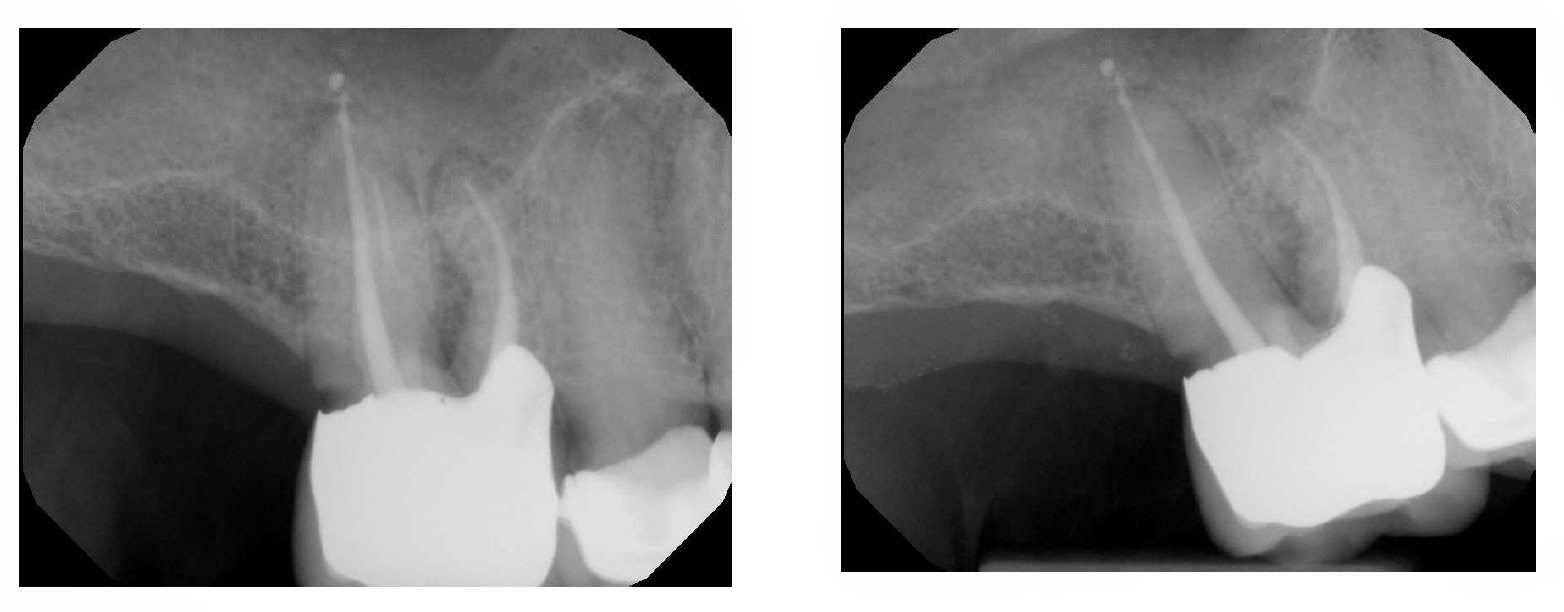

Root amputation is not a commonly performed procedure in my practice, but when it is, I like for it to look like this. In this case, the tooth is non-mobile – despite the bone loss around the DB root. While the distal margin is open, it is not carious and patient is not planning to replace the crown at this time. Pt understands that this procedures extends the life of the tooth. I explain that the short term prognosis is good. If the tooth does well, then replacement of the crown can be considered.